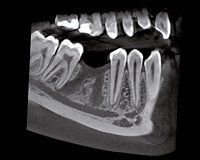

Vor dem implantologischen Eingriff muss eine umfassende Diagnostik erfolgen, um gesicherte Informationen über die Knochenstruktur zu erhalten. Neben den klinischen Befunden ist Röntgen das wichtigste Entscheidungskriterium für eine Implantation.

Die 3D-Diagnostik (Digitale Volumentomografie) ist die modernste und präziseste Röntgenmethode. Mit Hilfe der dreidimensionalen Darstellung der Kieferregion kann der optimale Implantationsort millimetergenau festgelegt werden.

Mit seiner hohen Aufnahmequalität lassen sich auch feinste Strukturen in Knochen und Gewebe erkennen...

...und Implantate punktgenau und vorausschauend planen.